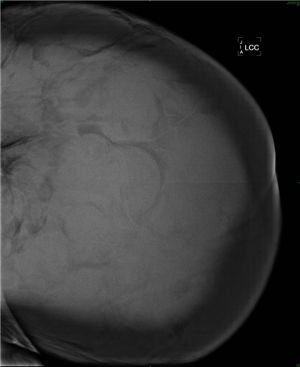

[아시아경제 신범수 기자]정상보다 25배나 큰 '거대유방'을 가진 여성이 건국대병원에서 성공적으로 축소수술을 받았다.건국대학교병원 유방암센터 양정현 교수와 성형외과 최현곤 교수팀은 최근 9kg에 달하는 거대 유방을 성공적으로 축소 수술했다. 43세의 이 여성 환자는 약 1년 6개월 전부터 유방이 커지기 시작해 일상생활이 불편할 정도로 심한 어깨와 허리 통증에 시달려왔다.진단 결과 왼쪽 유방이 5.4kg(사진), 오른쪽은 2.8kg에 달했다. 한국 여성의 통상적인 유방 무게는 0.2~0.25g이다. 의료진은 거대유방증 진단 하에 양측 유방 모두 300g 정도만 남겨 놓고 조직을 절제한 후 피부와 유두 성형을 했다. 수술 직후 환자의 체중은 63kg에서 54kg으로 9kg 감소했으며 합병증 없이 7일 만에 퇴원했다. 외과 양정현 교수에 따르면 우리나라에서는 지금까지 3.0kg 정도의 유방이 문헌에 보고됐으며 외국의 경우 12kg까지 보고된 적이 있다. 일반적으로 거대유방증은 호르몬 과다분비, 약물부작용, 임신, 종양 등이 주요 원인으로 알려져 있는데 이번에 수술한 환자의 경우는 특별한 원인을 발견할 수 없었다고 병원 측은 설명했다.신범수 기자 answer@<ⓒ세계를 보는 창 경제를 보는 눈, 아시아경제(www.asiae.co.kr) 무단전재 배포금지>